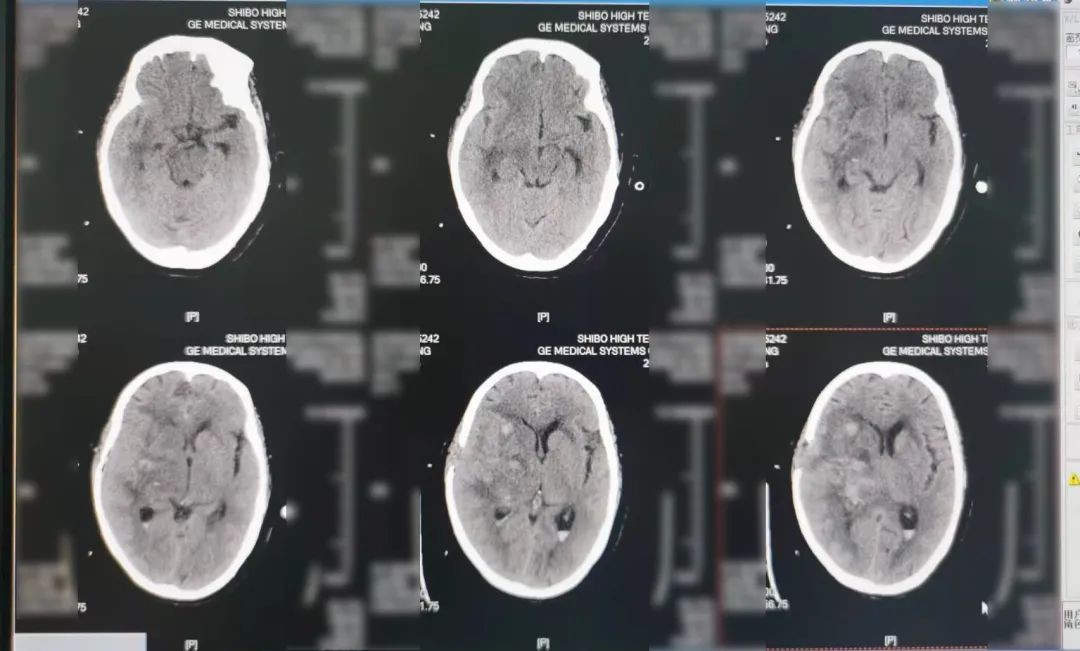

术后14天患者复查,血肿基本吸收